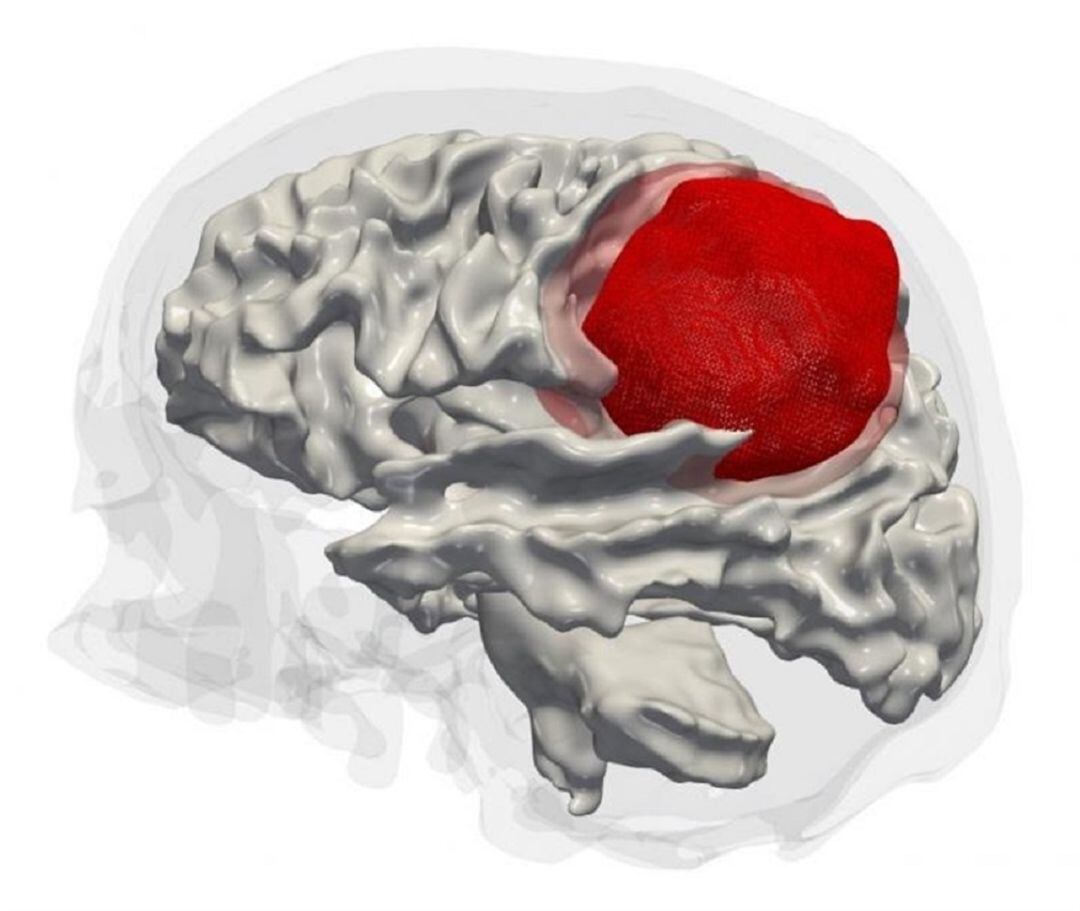

Investigadores del Instituto de Neurociencias UMH-CSIC en Alicante y el IMIB-Arrixaca de Murcia han descubierto cómo consigue el glioblastoma, el cáncer cerebral más frecuente y agresivo, invadir el tejido sano sin apenas resistencia, un hallazgo que podría convertirse en un 'talón de Aquiles' que logre frenar la progresión de este cáncer cerebral.

Concretamente, los investigadores han podido comprobar en un modelo de ratón que el bloqueo de esta autofagia anómala dificulta el desarrollo del tumor, al provocar la adhesión defectuosa del glioblastoma al pericito y, con ello, la muerte de las células cancerosas, por lo que se convierte en un objetivo terapéutico prometedor.